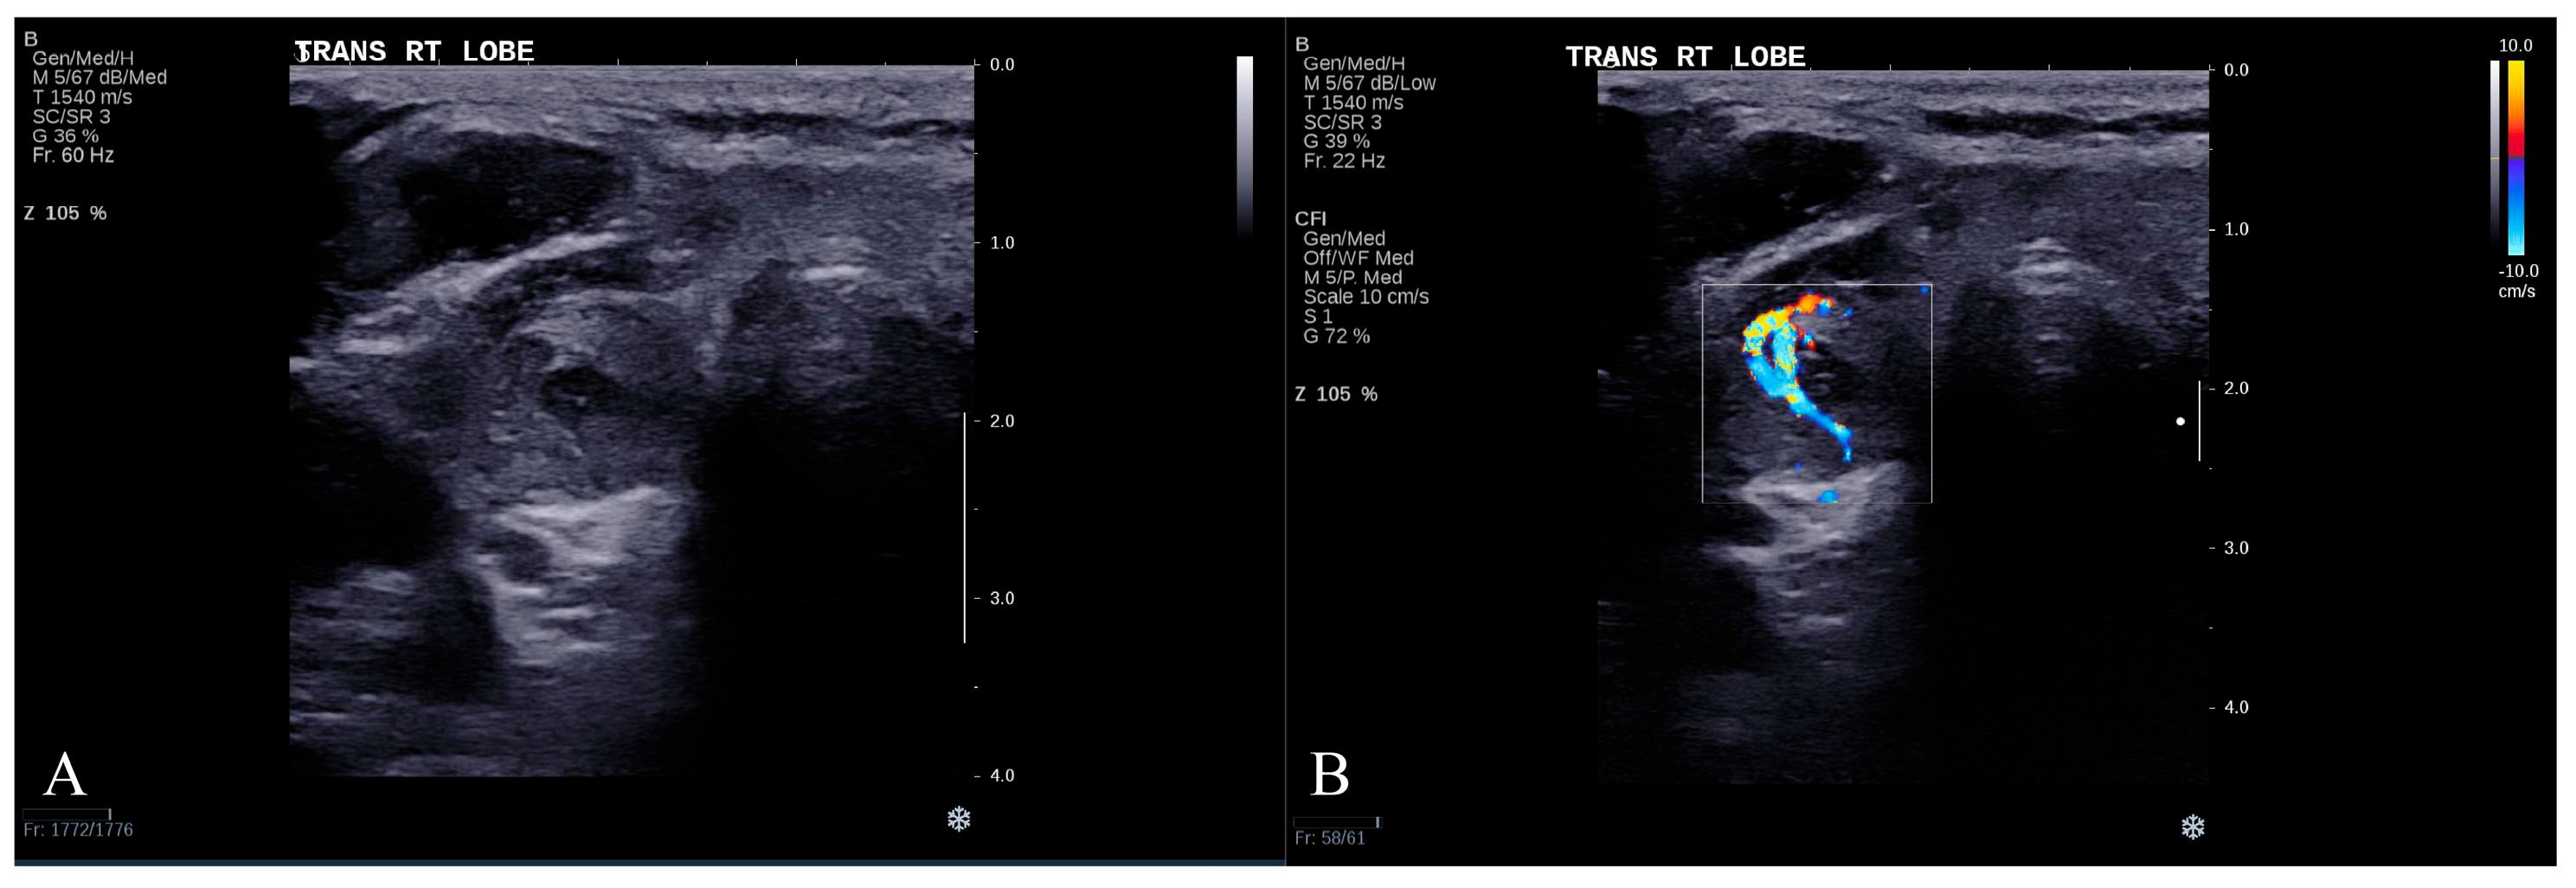

- Dual-modality analysis: This approach used grayscale ultrasound and CDUS images only. The following prompt was provided to ChatGPT-4o to direct its analysis: “Please act as a senior ultrasound physician with extensive experience in diagnosing thyroid nodules. I will upload multimodal ultrasound images of a patient’s thyroid nodule. To help you focus on the characteristics of the nodule itself, the uploaded images will only show the nodule and the surrounding thyroid tissue, excluding any other content that might interfere with the evaluation. The first image is a grayscale ultrasound image showing the largest transverse section of the nodule. The second image is a color Doppler ultrasound image of the nodule. Please analyze the nodule based on the uploaded images: First, describe the ultrasound characteristics of the nodule from the first image. Then, describe the blood flow information from the second image. Next, provide a detailed explanation of your diagnostic reasoning. Finally, give a clear diagnostic conclusion indicating whether the nodule is benign or malignant. Thank you.”

- Triple-modality analysis: This analysis used SWE measurements, grayscale ultrasound and CDUS images to offer an integrated evaluation approach. The prompt was adapted as follows: “Please act as a senior ultrasound physician with extensive experience in diagnosing thyroid nodules. I will upload multimodal ultrasound images of a patient’s thyroid nodule. To help you focus on the characteristics of the nodule itself, the uploaded images will only show the nodule and the surrounding thyroid tissue, excluding any content that might interfere with the evaluation. The first image is a grayscale ultrasound showing the largest transverse section of the nodule. The second image is a color Doppler ultrasound of the nodule. In addition, I will provide the results of shear wave elastography (SWE) for the nodule, indicating that the average stiffness measured by Young’s modulus is XX kPa. Please analyze the nodule based on this information: First, describe the ultrasound characteristics of the nodule from the first image. Then, describe the blood flow information from the second image. Next, incorporate the elastography results and provide a detailed explanation of your diagnostic reasoning. Finally, give a clear diagnostic conclusion indicating whether the nodule is benign or malignant. Thank you.”